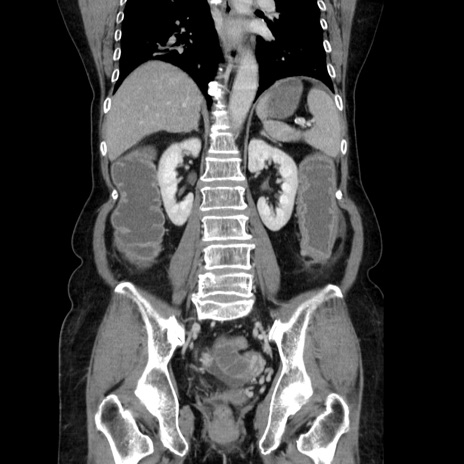

症例5(冠状断像)

【症例】70歳代女性

【主訴】お腹が張る

【現病歴】1週間くらい前から腹部膨満の自覚あり。昨日夜から増悪したため、本日救急外来受診。

【身体所見】意識清明、BT 36.5℃、BP 165/106mmHg、HR 80bpm、SpO2 98%、腹部:膨満、軟、自発痛・圧痛なし、触診にて不快感あり、腸蠕動音:減弱

【データ】WBC 12600、CRP 1.04